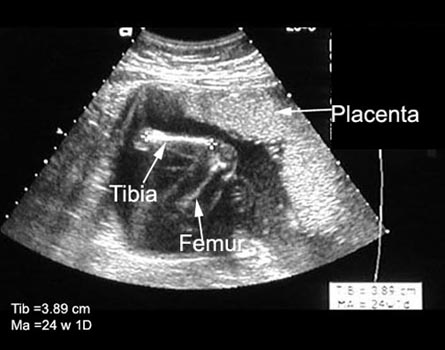

Measurements |